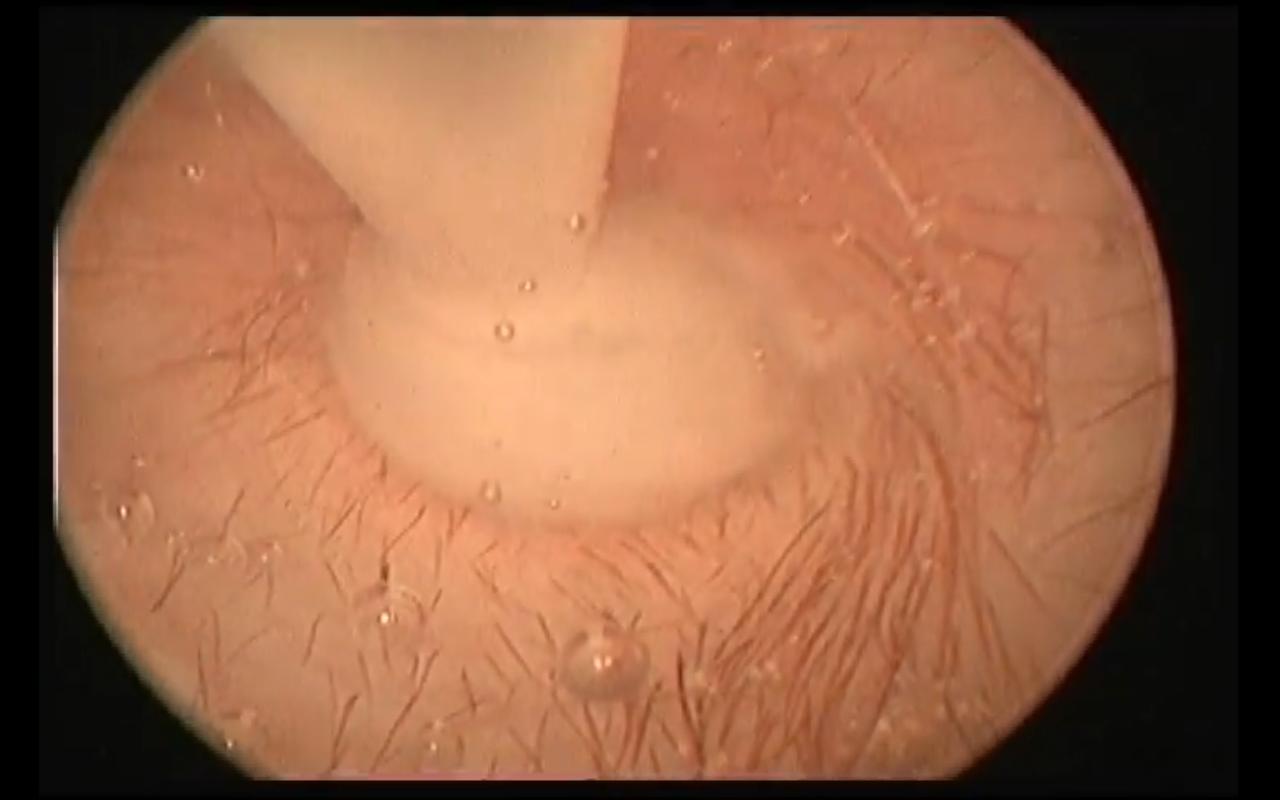

Treatment traditionally has consisted of performing a myringotomy,

making a small cut in the eardrum (tympanic membrane), followed by

flushing the middle ear to force out the mucus plug. (See photo at

right.) Topical and/or

Treatment traditionally has consisted of performing a myringotomy,

making a small cut in the eardrum (tympanic membrane), followed by

flushing the middle ear to force out the mucus plug. (See photo at

right.) Topical and/or

• myringotomy

Treatment

primarily has consisted of performing a myringotomy

(see photo at right), making a small cut in the eardrum (tympanic

membrane), followed by flushing the middle ear to force out the mucus

plug. The photograph at right is of a myringotomy in progress. The ring

in the middle of the photo is the eardrum. The tube tip at the top is

the device used to flush the inner ear and force out the mucus. You may

Treatment

primarily has consisted of performing a myringotomy

(see photo at right), making a small cut in the eardrum (tympanic

membrane), followed by flushing the middle ear to force out the mucus

plug. The photograph at right is of a myringotomy in progress. The ring

in the middle of the photo is the eardrum. The tube tip at the top is

the device used to flush the inner ear and force out the mucus. You may